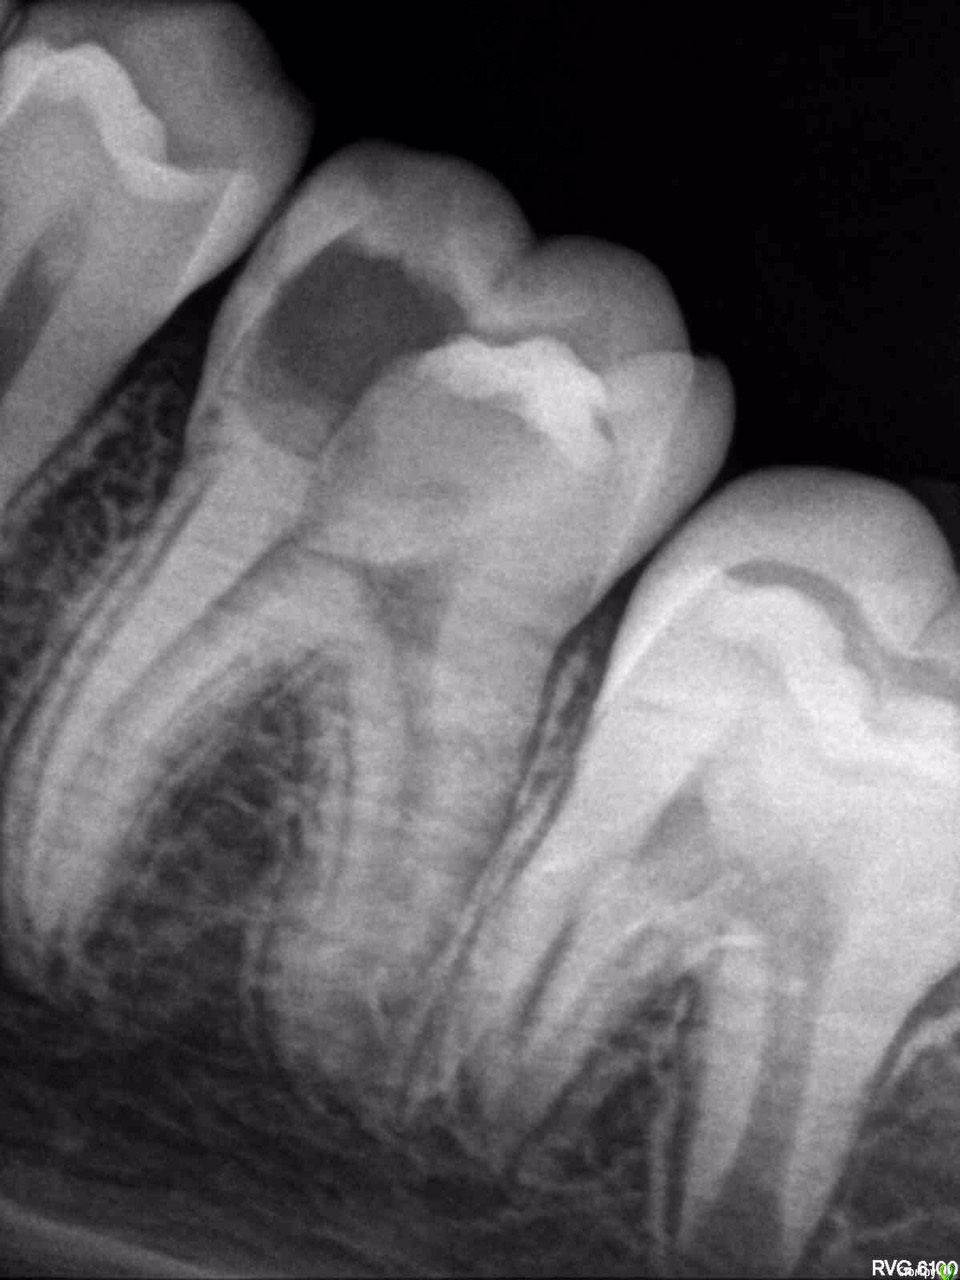

Masha01 Опубликовано 26 февраля, 2016 Поделиться Опубликовано 26 февраля, 2016 Между первым и вторым фото два года. Апексогенез на мта. Ссылка на комментарий

Masha01 Опубликовано 27 февраля, 2016 Поделиться Опубликовано 27 февраля, 2016 мта же платно делаете?и после формирования вы его планируете переливать полноценным эндо или так оставлять?я в частной работаю. Полноценное эндо не планирую, т.к. есть дентинный мостик Ссылка на комментарий